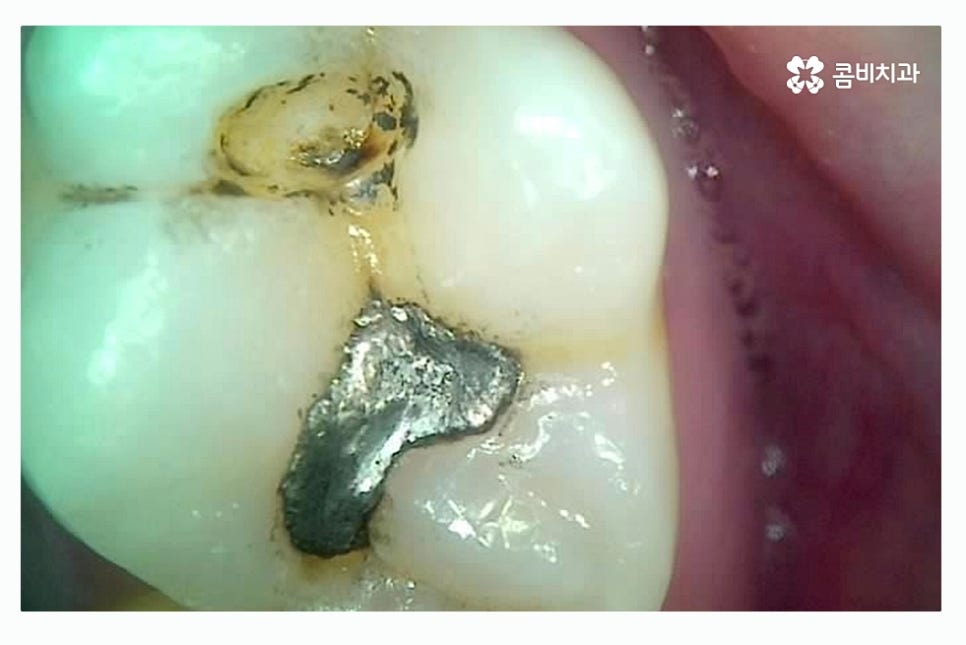

과거에 치료를 했던 레진, 인레이 혹은 아말감과 같은 치과용 치료 재료가

오랜 세월이 지나면서 마모, 접착 불량, 크랙 등의 이유로 교체가 필요한 시기에

치료가 안될 경우 치아 내부로 침이나 음식물이 유입이 되면서

충치가 발생하는 사례가 종종 있어요.

이때 교체 시기를 잘 지키는 것이 중요한데 환자분들의 구강 상태는

개인차가 있기 때문에 정기 검진을 받는 것이 치아에 문제가

생기더라도 초기에 빠른 치료를 할 수 있는 방법이라고 할 수 있어요.